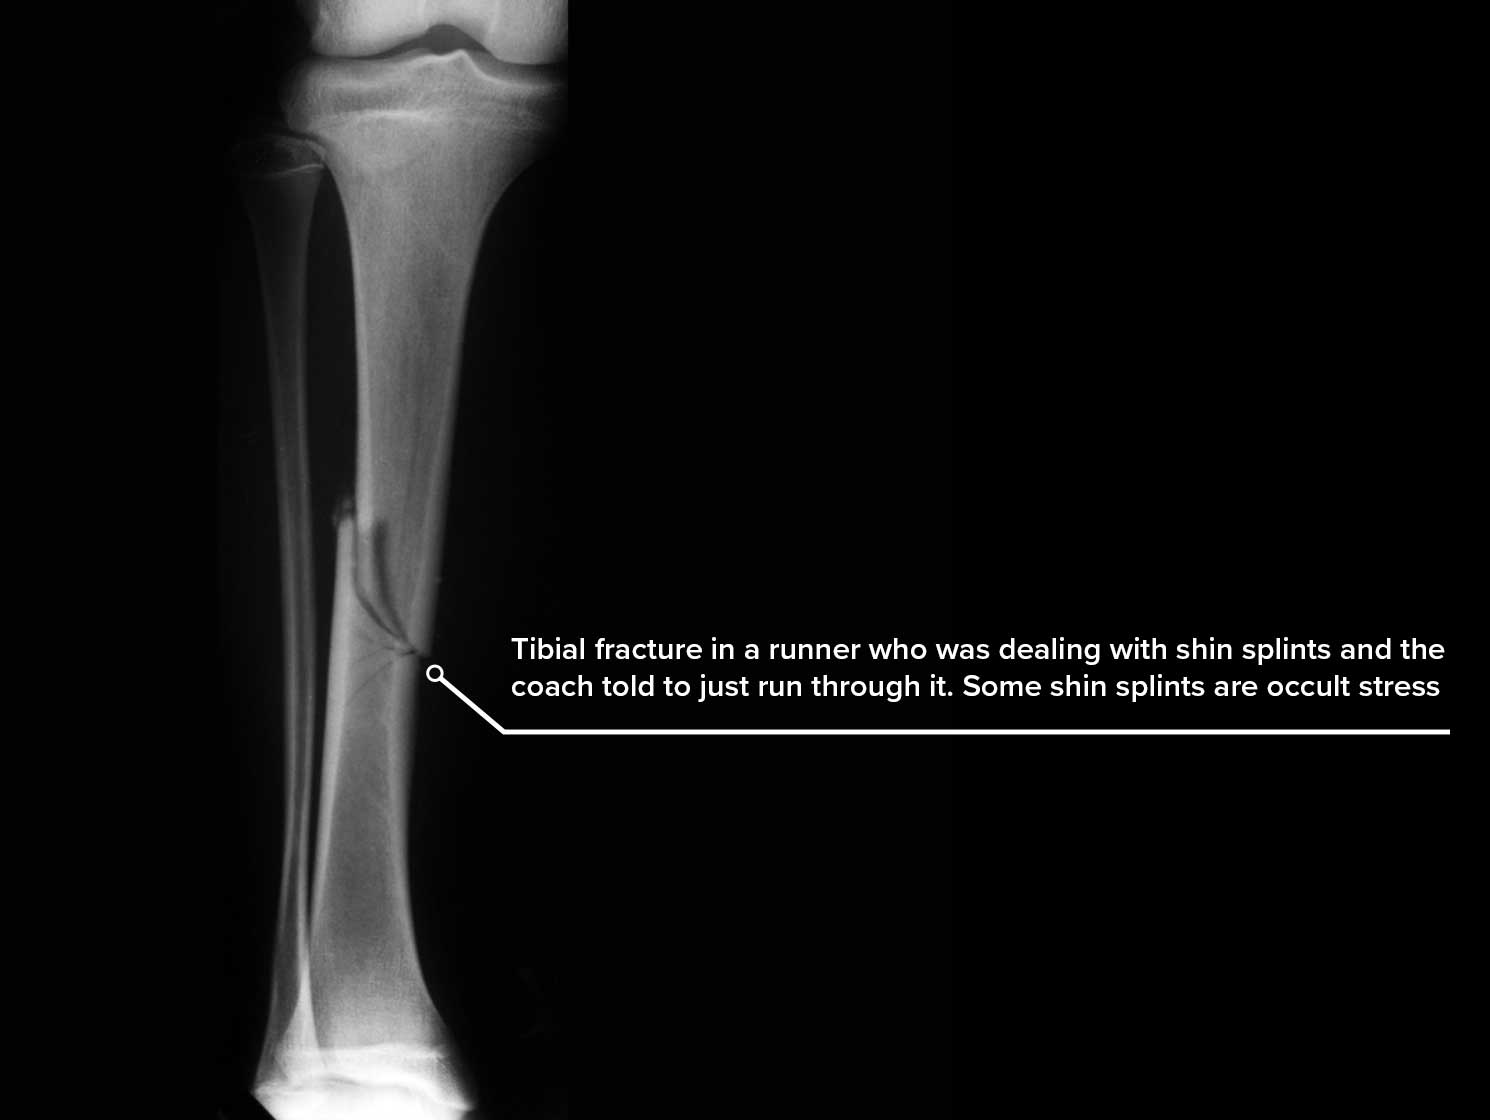

The two most common muscles that appear to be indicated are posterior tibial and soleus. Of course, both are decelerators of contact phase pronation. Most runners land inverted with their heels and pronate their subtalar joints to some degree (at times very excessive). This can be influenced by the shoes they wear, the need for custom orthotic devices, their speed, their tendency to overstride, the terrain, etc. As normal pronation, important for shock absorption and leg internal rotation at contact, gives way to excessive amounts, the medial instability produced can be devastating. 10-15% of all runners will complain of shin splints in any given year.. Some have occult stress fractures, disguised as mere shin splints, that shouldn’t be run through. Some patients with shin splints need primary shock absorption, yet most in my practice were helped by controlling excessive amounts of pronation. So what are the key points of this article in summary? They include:

- The authors imply that shin splints were seen more in beginning runners, which I would agree with (therefore, shin splints in an experienced runner should be worked up for stress fractures of the tibia)